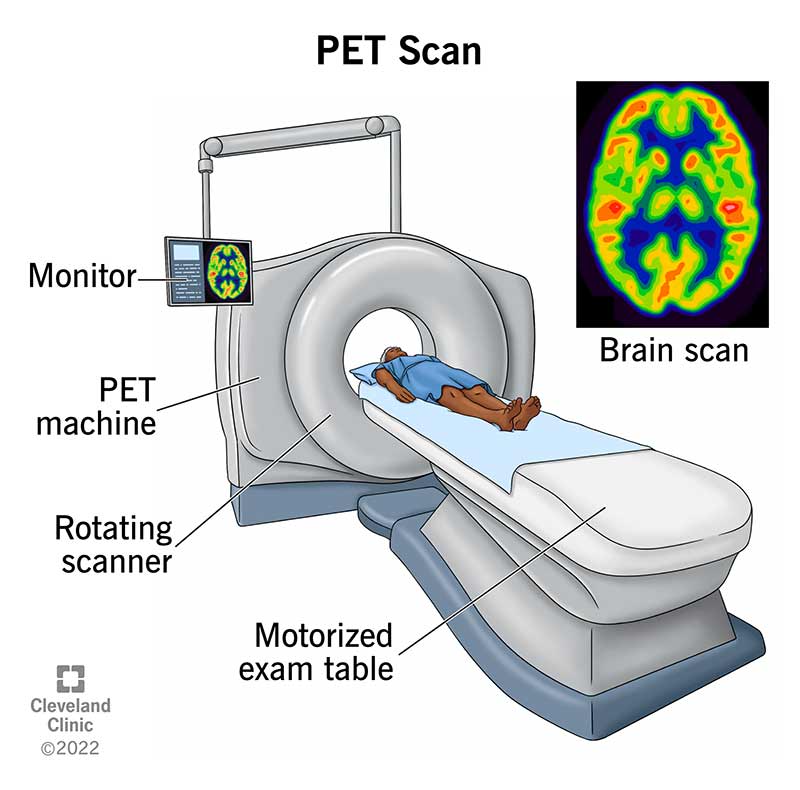

Enhance your business with our stunning commercial Cardiac Pet/ct collection of numerous professional images. optimized for commercial use with truck, vehicle, and automobile. ideal for corporate communications and branding. Discover high-resolution Cardiac Pet/ct images optimized for various applications. Suitable for various applications including web design, social media, personal projects, and digital content creation All Cardiac Pet/ct images are available in high resolution with professional-grade quality, optimized for both digital and print applications, and include comprehensive metadata for easy organization and usage. Discover the perfect Cardiac Pet/ct images to enhance your visual communication needs. Our Cardiac Pet/ct database continuously expands with fresh, relevant content from skilled photographers. Reliable customer support ensures smooth experience throughout the Cardiac Pet/ct selection process. Professional licensing options accommodate both commercial and educational usage requirements. Multiple resolution options ensure optimal performance across different platforms and applications. Regular updates keep the Cardiac Pet/ct collection current with contemporary trends and styles. Each image in our Cardiac Pet/ct gallery undergoes rigorous quality assessment before inclusion. Time-saving browsing features help users locate ideal Cardiac Pet/ct images quickly. The Cardiac Pet/ct archive serves professionals, educators, and creatives across diverse industries. Comprehensive tagging systems facilitate quick discovery of relevant Cardiac Pet/ct content.